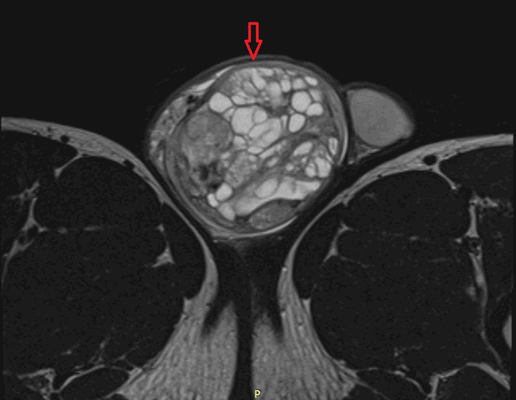

Рисунок 3. - тератома яичника а -УЗИ, б — МРТ.

Злокачественные тератомы обычно проявляются неспецифической клинической картиной, которая связана с наличием опухоли:

- увеличенный объем живота;

- боль;

- нарушение менструального цикла (наблюдается не всегда).